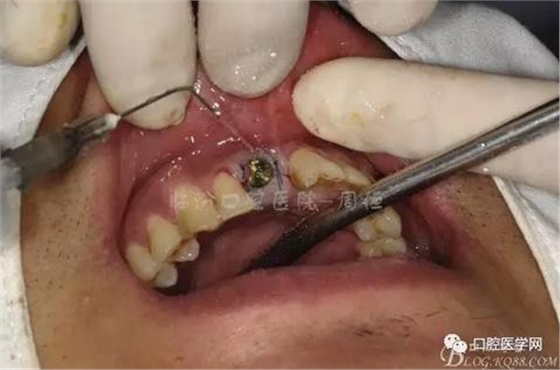

圖6 術中植入植體